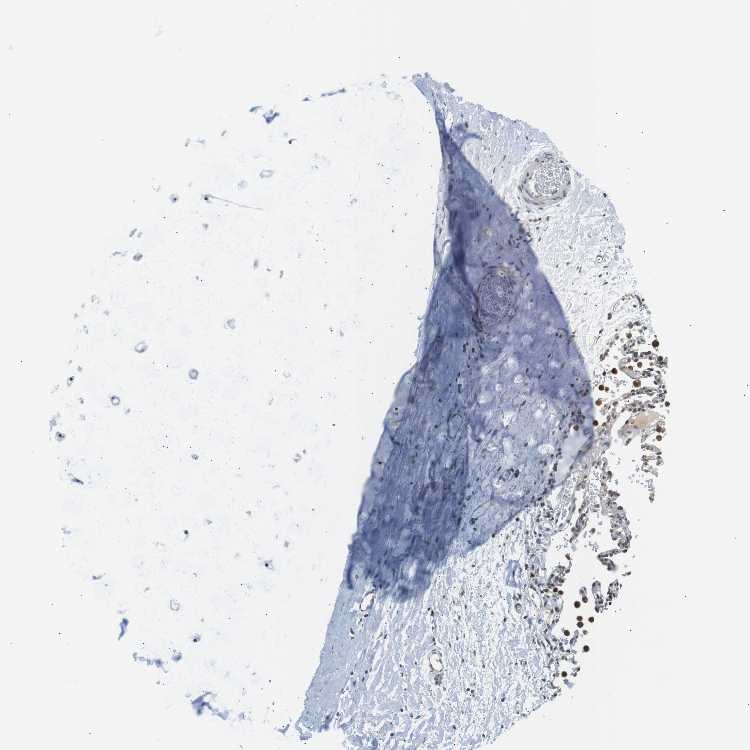

SOFT TISSUE 1 - Antibody stainingi

Antibody staining in the annotated cell types in the current human tissue is reported as not detected, low, medium, or high, based on conventional immunohistochemistry profiling in selected tissues. This score is based on the combination of the staining intensity and fraction of stained cells.

Each image is clickable and will lead to virtual microscopy that enables deeper exploration of all samples and also displays staining intensity scores, fraction scores and subcellular localization as well as patient and tissue information for each sample.

Antibody HPA000399Antibody HPA015752

Chondrocytes LowMedium

Fibroblasts LowMedium

Peripheral nerve Not detectedHigh

SOFT TISSUE 2 - Antibody stainingi

Peripheral nerve Not detectedMedium